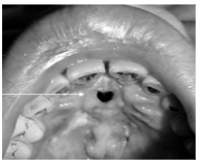

ORAL:

*Jaw lesions → pain, swelling, numbness, tooth mobility

*Amyloid deposits throughout body: tongue, vestibule